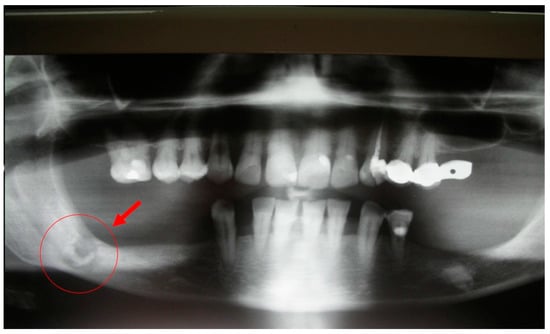

5.2. Case Report 2

A 65-year-old female patient developed MRONJ after the administration of intravenous DB. The lesion has been radiologically identified through OPT and is located in teeth 36–38 (Figure 13).

Figure 13.

OPT of initial lesion pointed by the circle.